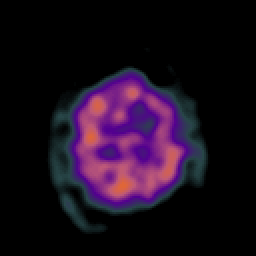

Vascular Malformation (at rest): perfusion SPECT study #1 -- Slice #21

[Home][Help][Clinical] Slice 21